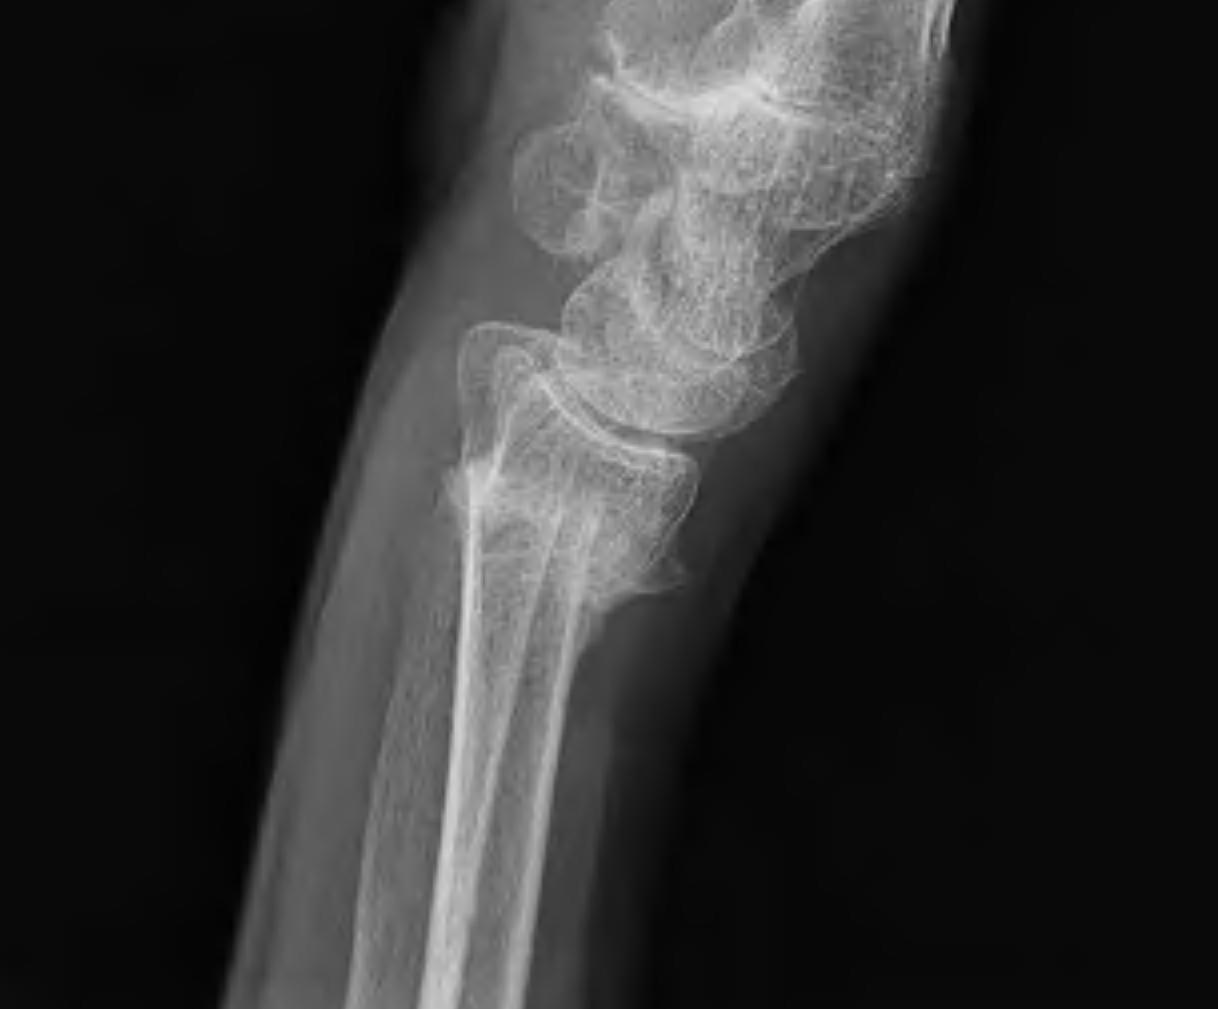

Dorsal opening wedge osteotomy

Distal Radial Malunion Dorsal OsteotomyDistal Radial Malunion Dorsal Osteotomy

Advantage

Lengthens the distal radius

May be easier to correct in coronal and sagittal plane

Disadvantage

Dorsal approach / dorsal plate - extensor tendon issues

Technique

3 / 4 dorsal approach

- expose distal radius

- can use half pins to control distal fragment

- protect structures with homan retractors

- osteotomy with microsagittal saw

- correct radial articular surface in sagittal & coronal planes

- trapezoidal bi-cortical iliac crest autograft / synthetic graft

- dorsal locking plate